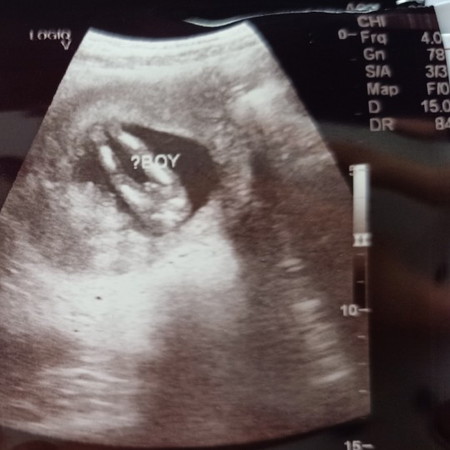

ผุ้ชาย

12w3d ภาพจะชัดขนาดนี้เรยหรอค้ะ !

บ้านนี้ซาวด์หมอบอกเพศตั้งแต่11w

ไม่มีอะไรให้กังขา 🙍♂️ ชัดมากค่ะ

บ้านนี้ผุ้ชายชัดเจนมากค่ะแม่

นิ้จากคลีนิคแพทย์เรย ค่ะ แต่ไม่คิดว่าจะชัดขนาดนี้